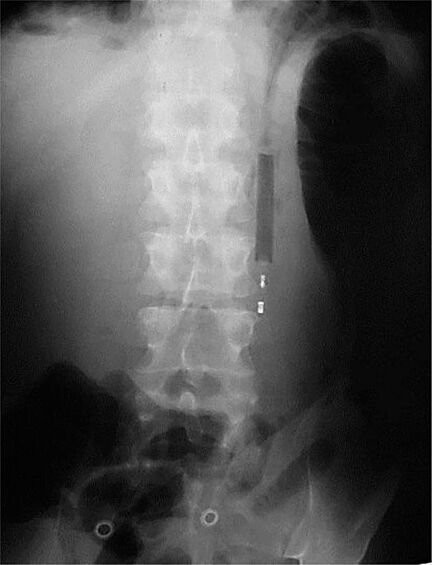

12 рентген‑фотографий, которые доказывают: идиотизм неистребим

Зачем и почему люди глотают разные странные вещи? Никто не знает точно, но медики утверждают, что таких “умников” гораздо больше, чем мы думаем.

Рентгенологи — люди с особо развитым чувством юмора. То, что они порой видят на снимках, у нормального человека вызовет настоящую истерику — а они только хмыкнут и отправят к хирургу. Что поделать, не расстраиваться же из-за каждого курьеза.